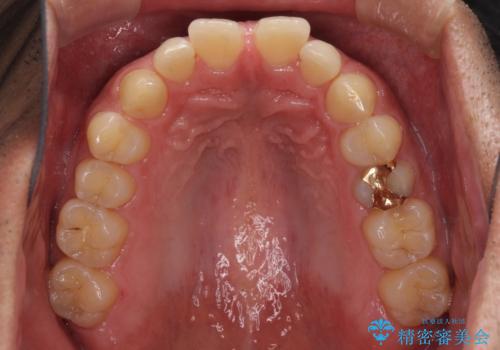

- 上顎前歯の突出感とすきっ歯を気にして来院された患者様です。

奥歯の咬み合わせを見ると、下顎に対して上顎が前方に位置していたため、補助装置により上顎歯列全体を後方に移動させ、その後インビザラインにて歯列全体を整えることとしました。